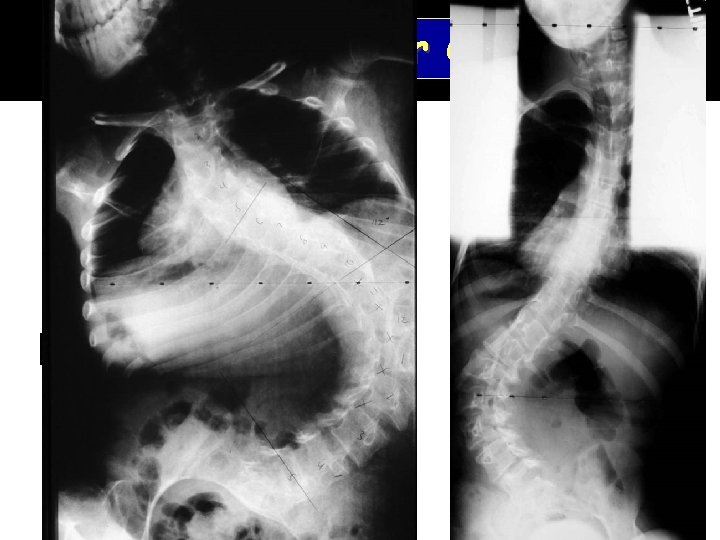

Neuromuscular Curves

Pelvic Obliquity